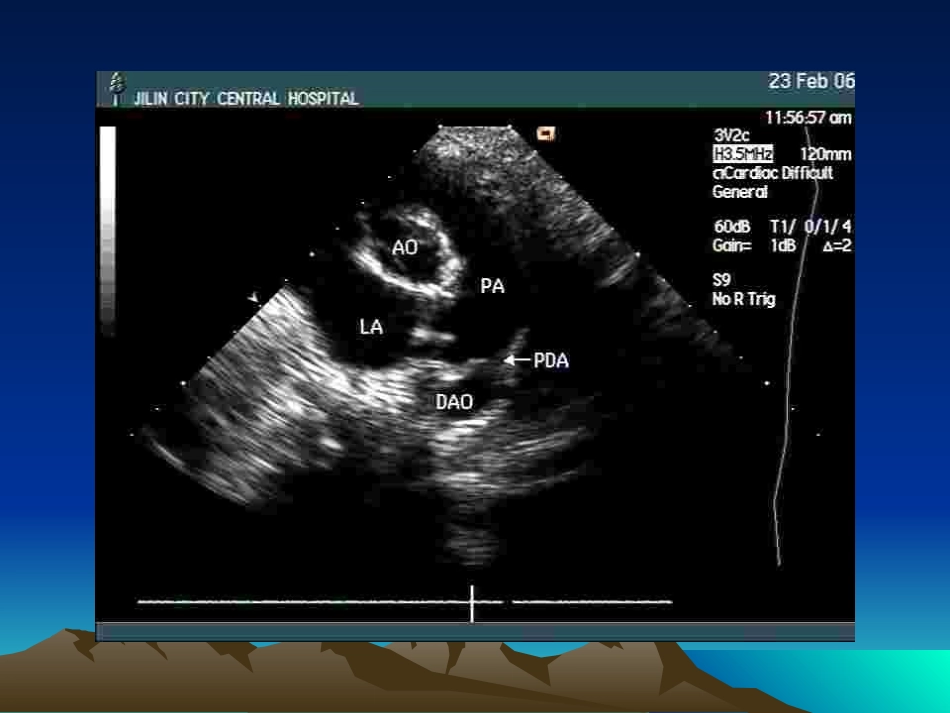

先心病介入治疗先心病介入治疗——PDAPDA动脉导管未闭(动脉导管未闭(PDAPDA)封堵术)封堵术概述概述■■19671967年年PostmannPostmann首先用海锦塞成功堵闭首先用海锦塞成功堵闭PDAPDA■■19791979年年RashkindRashkind双面伞堵闭装置问世双面伞堵闭装置问世■■19911991年年SiderisSideris纽扣式堵闭装置用于临床纽扣式堵闭装置用于临床由于适应症不广,鞘管过粗,操作复杂,由于适应症不广,鞘管过粗,操作复杂,并发症多等不能在临床广泛推广应用并发症多等不能在临床广泛推广应用■■19921992年年CombierCombier应用弹簧圈堵闭小应用弹簧圈堵闭小PDAPDA■1997■1997年年MasuraMasura应用蘑菇伞装置关闭应用蘑菇伞装置关闭PDAPDA上述二种方法方法简单、安全、有效,并发症少。成为目前关闭上述二种方法方法简单、安全、有效,并发症少。成为目前关闭PDAPDA理想的方法理想的方法Amplanter堵闭器封堵器封堵器蘑菇伞堵闭要求大于最窄处3-6mmDAODAO造影无分流造影无分流主动脉造影显示小PDA并发症并发症11)堵闭器脱落)堵闭器脱落22)溶血)溶血33)心律失常,血管并发症)心律失常,血管并发症适应症适应症11)年龄>)年龄>33月,体重>月,体重>4.5Kg4.5Kg,单纯,单纯PDAPDA或合并其它先心病可通过导管介入治疗者,或合并其它先心病可通过导管介入治疗者,如如ASDASD、、PSPS、、ASAS22))PDA≤2.5mmPDA≤2.5mm选用弹簧圈堵闭选用弹簧圈堵闭>>2.5mm2.5mm选用蘑菇伞选用蘑菇伞临床意义临床意义目前PDA绝大多数中采用介入治疗,国内已普遍开展,但中长期随诊是今后的方向。X导管下封堵术